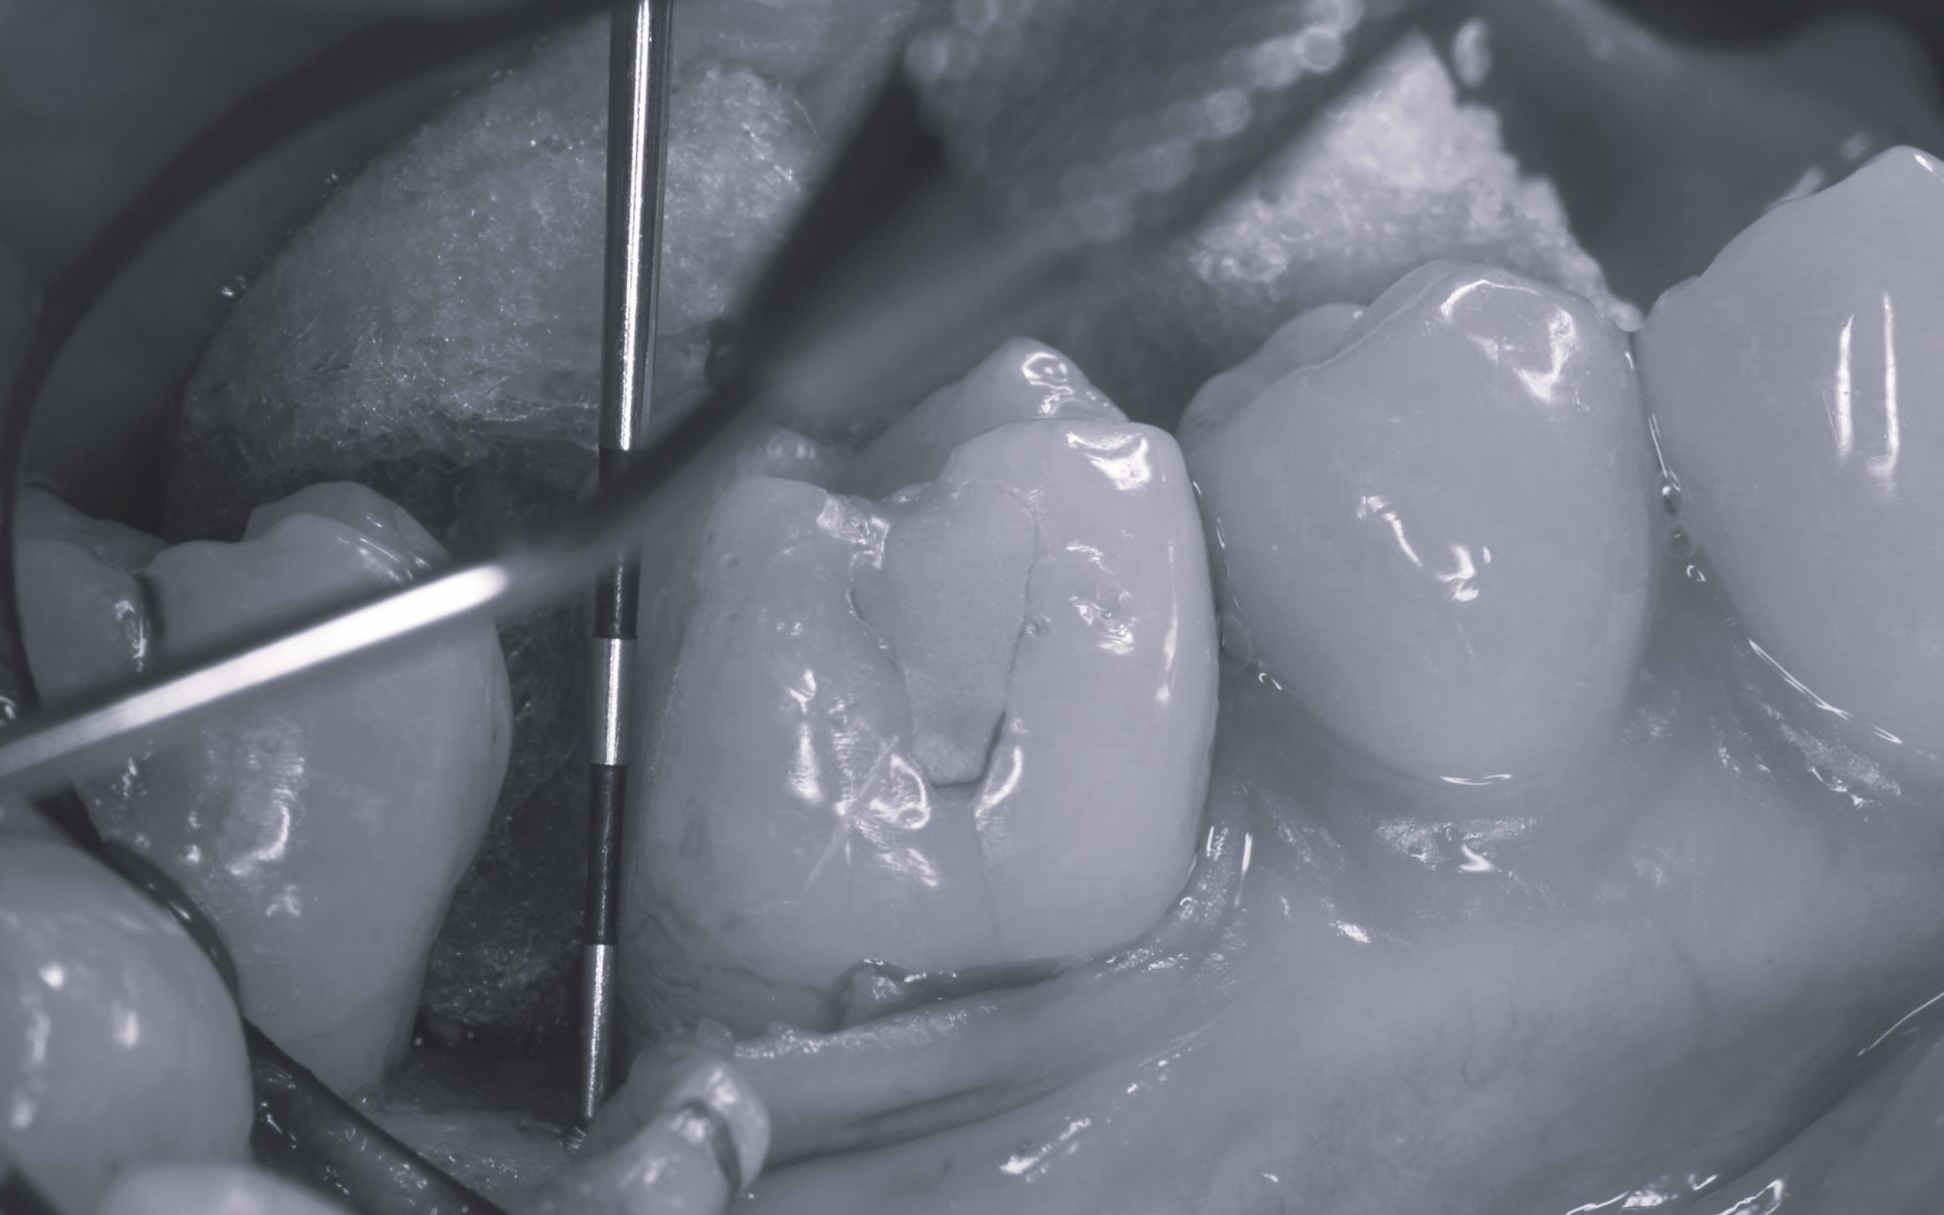

土台が完成したあとは、被せ物を作製するための精密な型取りを行います。

被せ物(クラウン)の素材には、天然歯に近い透明感をもちながら、優れた耐久性を兼ね備えたジルコニアセラミックを採用しました。

精密な型取りを行いました。